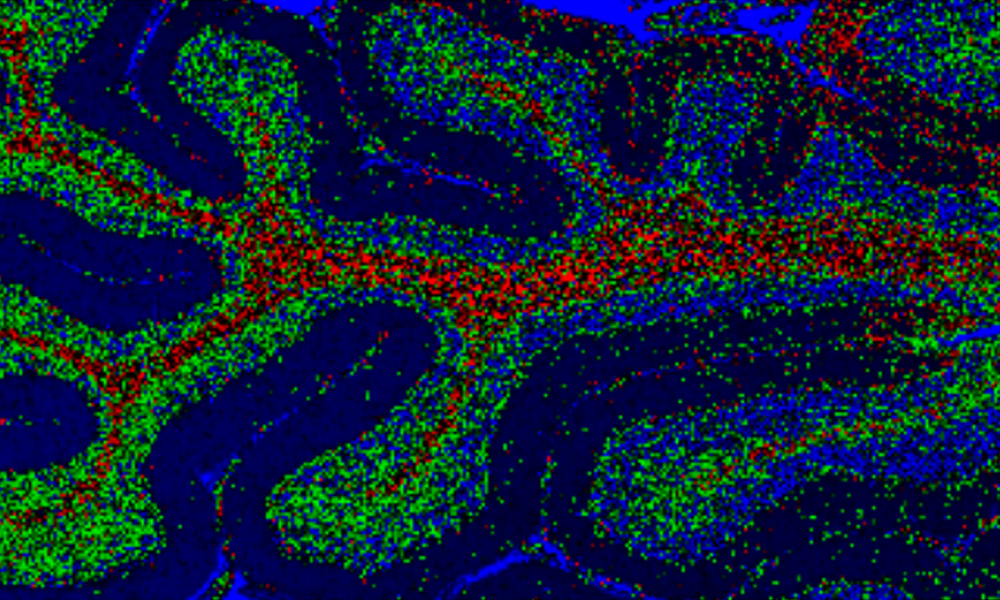

Imagem Raman de tecido do cérebro (jpg)

Último - Espectroscopia Raman